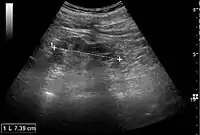

Acute pyelonephritis with increased cortical echogenicity and blurred delineation of the upper pole.[20]

Ultrasound findings that indicate pyelonephritis are enlargement of the kidney, edema in the renal sinus or parenchyma, bleeding, loss of corticomedullary differentiation, abscess formation, or an areas of poor blood flow on doppler ultrasound.[21] However, ultrasound findings are seen in only 20% to 24% of people with pyelonephritis.[21]